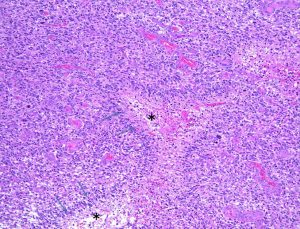

glioblastoma, IDH-wild typeのHE染色像

クリックすると画像が拡大します。

弱拡大像で、壊死necrosis (*)を囲む腫瘍細胞核の偽柵状配列 pseudopalisading pattern (→)を示す。

HE x100.